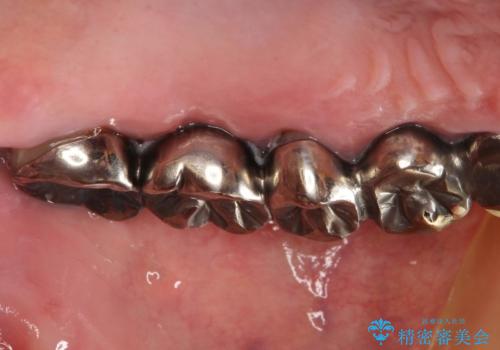

虫歯だらけ、歯周病 崩壊した口腔の再建 フルマウスリコンストラクション

かみ合わせの力が非常に強く、夜間の歯ぎしり・食いしばりもひどかったため、奥歯はメタルオクルーザルの設計でかぶせ物を製作しています。

かぶせ物の種類:PFZ / PFM metal occlusal